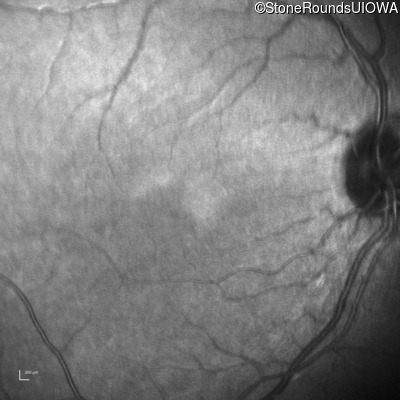

Infrared Fundus Photograph - Right - 10/200

Exemplar

Infrared Fundus Photograph - Left - 10/100